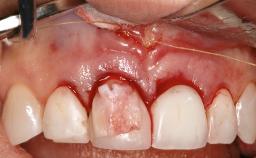

Resective Surgical Treatment of Peri-Implantitis Including Implantoplasty

In this case, Myroslav Solonko, Ignacio Sanz Sánchez and Mariano Sanz present a treatment that aims to eliminate exposed implant threads by modifying the implant surface, converting a moderately-rough surface into a smooth surface.

A 63-year-old male patient was referred to the post-graduate periodontal clinic of the Complutense University of Madrid for the treatment of peri-implantitis. According to the patient’s record, all his maxillary teeth had been extracted ten years previously due to severe periodontitis, and a full-mouth implant-supported restoration on eight implants was placed. No supportive periodontal therapy was provided apart from occasional check-ups by the restorative dentist.